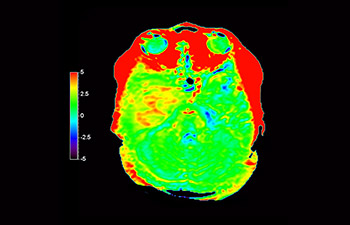

In a society where neurological disorders represent a heavy burden, Philips is committed to provide superb diagnostic clarity and treatment guidance for all patients. Today, although MR is the gold standard in neuro oncology imaging, its accuracy in tumor grading and treatment follow up assessment can be further improved. 3D APT (Amide Proton Transfer) is a unique, contrast-free, brain MR imaging method addressing the need for more confident diagnosis in neuro oncology. 3D APT uses the presence of endogenous cellular proteins, to produce an MR signal that directly correlates with cell proliferation, a marker of tumoral activity. 3D APT can support trained medical professionals in differentiating low grade from high grade gliomas and, in differentiating tumor progression from treatment effect1.

with 3D APT